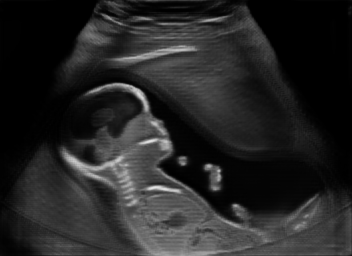

Real in-vivo images. 22 ultrasound sequences were collected using a GE Voluson E8 machine during standard fetal screening exams of 8 patients. Each sequence is several seconds long. We extracted all 4427 frames and resize them to , see Fig. 2 for some examples. The resulting image set was randomly split into training-validation-test sets by a 80-10-10% ratio.

Discussion. Note that, despite both being fetal images, the simulated and the real images have substantially different anatomical contents, which makes the translation task extremely challenging. Nevertheless, our proposed framework is able to generate images with appearance strikingly close to real images, with far superior realism than its competitors. Besides sim-to-real translation, given its multi-domain conditional nature, our proposed framework without any further training can also translate images between the other domains, e.g. seg-to-real or seg-to-sim, with examples presented in Fig. 5.